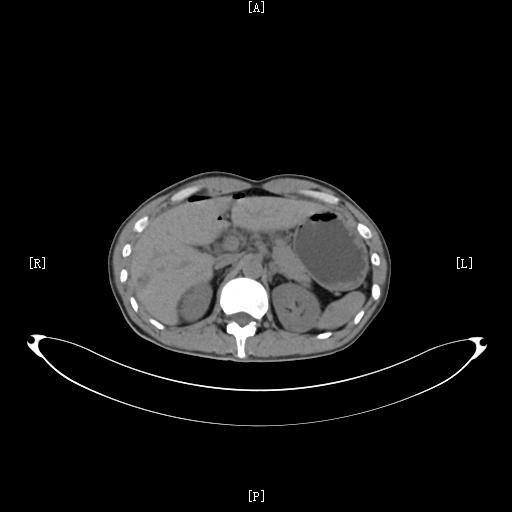

如果出现上述类似的症状,建议及时到医院筛查排出肝脓肿。主要的检查项目常常为 查血和超声检查 。实验室查血检查常常 白细胞计数明显增高 ;超声检查常常可以 明确其部位和大小 ,阳性诊断率可以达到95%以上,是首选检查;当然, 必要时也可以做CT检查 ,CT检查能够全面评估病灶以及周围脏器的情况,是非常好的一项辅助检查方法。

肝脏肿瘤的疼痛常常不是特别典型,所以及时筛查非常重要,对于肝癌,主要的筛查方法包括: 查血清甲胎蛋白(AFP),超声检查,CT检查和MRI检查 。AFP对肝癌有比较高的特异性,很多肝癌患者都有AFP的升高;而影像学的超声,CT和MRI检查是诊断肝癌以及其他肝脏肿瘤最主要的方法。

急性胆囊炎常常通过医生的 体格检查,结合查血,超声及CT检查 可以确诊。体格检查常常会有右上腹胆囊区域的压痛;查血常常会有白细胞的升高,而超声和CT检查可以观察胆囊大小,胆囊壁是否增厚,胆囊周围有无水肿,是诊断胆囊炎必不可少的辅助检查。

而对于胆囊及胆道结石的诊断,主要还是依靠 超声检查 。对于胆囊结石,超声诊断准确率一般都非常高,而对于部分胆道结石,需要借助CT或者MRCP检查进行确诊。

3、胆囊及胆道肿瘤。比如胆囊癌、胆管癌之类的。肿瘤引起的腹痛常常没有特异性,以隐痛比较多见。如果继发了胆囊炎,还可能和胆囊炎症状类似。所以对于胆囊肿瘤,最好的方法还是通过影像学检查明确。比较好的检查方法是CT或者MRI检查。

而如果怀疑是肾脏疾病,可以考虑进行 超声以及CT检查 ,影像学检查仍然是发现肾脏疾病最主要的方法。